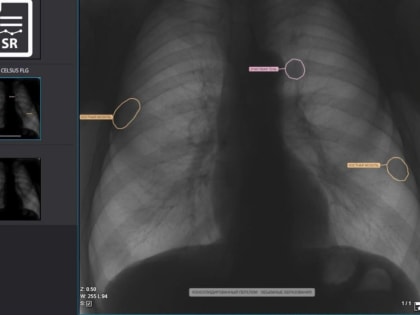

Искусственный интеллект помогает медицине Липецка

Новые технологии значительно ускоряют диагностику заболеваний легких.